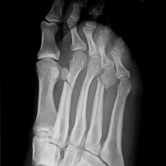

Röntgenbilder